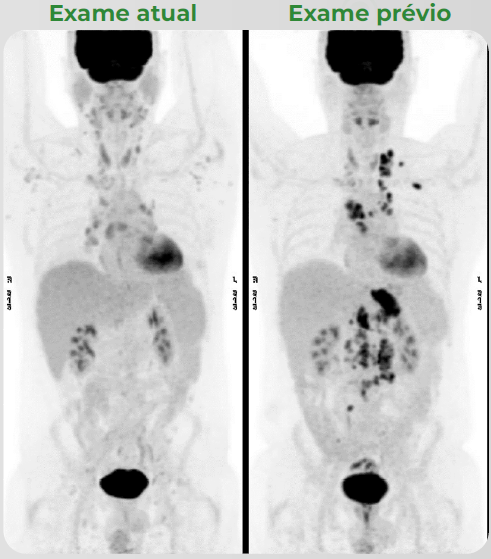

Caso clínico: Tratamento de paciente com Câncer de Esôfago avançado com PPC> 10 em 1L O caso clínico compartilhado pela dra. Marcela Crosara, traz detalhes sobre o tratamento em 1L de paciente com Câncer de Esôfago metastático CPS> 10.